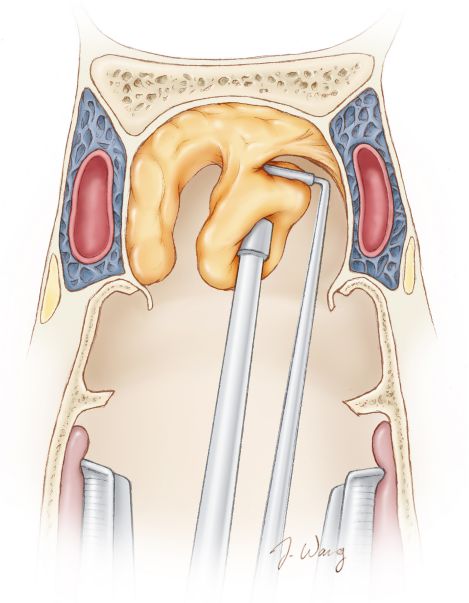

图6. 垂体大腺瘤切除的第一步为瘤内持续减压。环状刮匙从肿瘤下极刮除并使用吸引器吸除肿瘤。标准化的瘤内减压建议按照下方、侧方、上方的顺序进行。此顺序可避免鞍膈过早塌陷影响后续肿瘤切除。鞍膈过早暴露和塌陷可能阻碍术者视野,影响肿瘤根治性切除,并增加了鞍膈破裂的风险。

肿瘤中央部分在手术前期需避免切除,不当的切除可能使鞍膈塌陷,继而遮挡肿瘤侧方。肿瘤上方部分的操作需小心谨慎,因其有损伤垂体柄的风险。(引自Tew, van Loveren, Keller*,有改动)